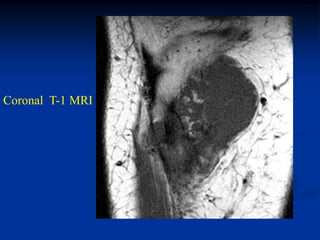

Coronal T-1 MRI